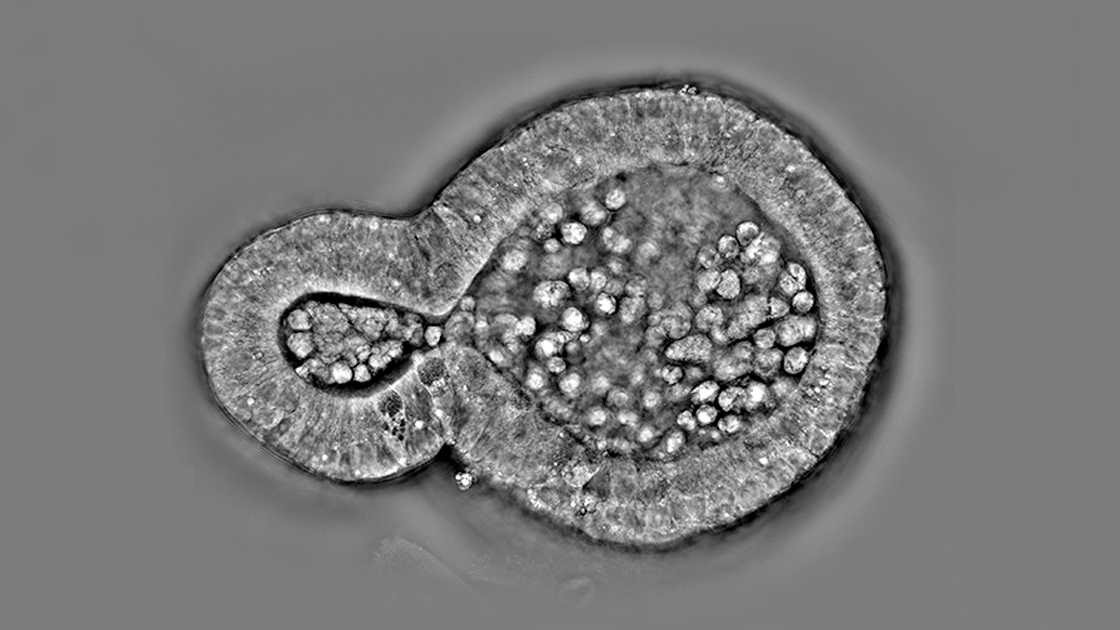

HT-X1 Plus mở rộng phạm vi của Holotomography đến nhiều loại mẫu vật phức tạp hơn nữa, bao gồm các cơ quan nhân tạo dày đặc, các lát cắt mô và các vi sinh vật chuyển động nhanh. Đây là một nền tảng tạo ảnh Holotomography hiện đại, được thiết kế để cung cấp cho các nhà nghiên cứu độ chính xác, hiệu quả và độ tin cậy cần thiết để thúc đẩy tương lai của khám phá sinh học và y sinh học.

Chụp ảnh độ phân giải cao các mẫu sinh học 3D

Các tính năng mới của HT-X1 Plus đặc biệt có lợi cho nghiên cứu liên quan đến nuôi cấy 3D, cho phép điều tra chi tiết các cơ quan nhân tạo dày đặc và các lát cắt mô nguyên vẹn. Nền tảng này tích hợp các nguồn sáng bước sóng dài, cải thiện độ xuyên thấu và giảm nhiễu tán xạ, để đạt được hình ảnh 3D rõ nét hơn. Ngoài ra, thuật toán tái tạo 3D tiên tiến giúp tăng cường hơn nữa cả độ rõ nét và độ chính xác của hình ảnh, mang lại chất lượng hình ảnh vượt trội cho hình ảnh sinh học 3D.